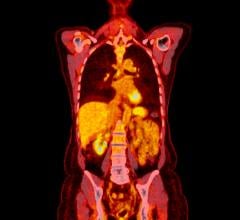

June 12, 2015 - Siemens' PETNET Solutions Inc. has entered into a nationwide agreement with U.K.-based Blue Earth Diagnostics Ltd. for the exclusive commercial manufacturing and distribution of Fluciclovine (18F), an investigational positron emission tomography and computed tomography (PET/CT) radiopharmaceutical. Fluciclovine (18F) is being studied for prostate imaging in clinical trials conducted in the United States, Japan, Italy, Norway, Sweden and Finland. The F-18-based radiopharmaceutical has a long half-life, which may facilitate its geographical distribution to clinical trial sites and then to clinical imaging centers once it gains approval from the U.S. Food and Drug Administration (FDA).

Prostate cancer is the second-leading cause of cancer in men worldwide, with 220,800 men expected to be diagnosed in 2015 in the U.S. alone. Currently, approved diagnostic options for prostate cancer include PET/CT scans using an injectable radiopharmaceutical to evaluate the extent of metastatic disease specifically for soft tissues and/or bony anatomy.